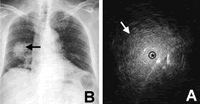

图 1例67岁细菌性肺炎患者的胸片和EBUS表现

胸片示右中叶外周占位性病变(A),EBUS示病变内均质回声和同心圆回声影像(B)。, 百拇医药